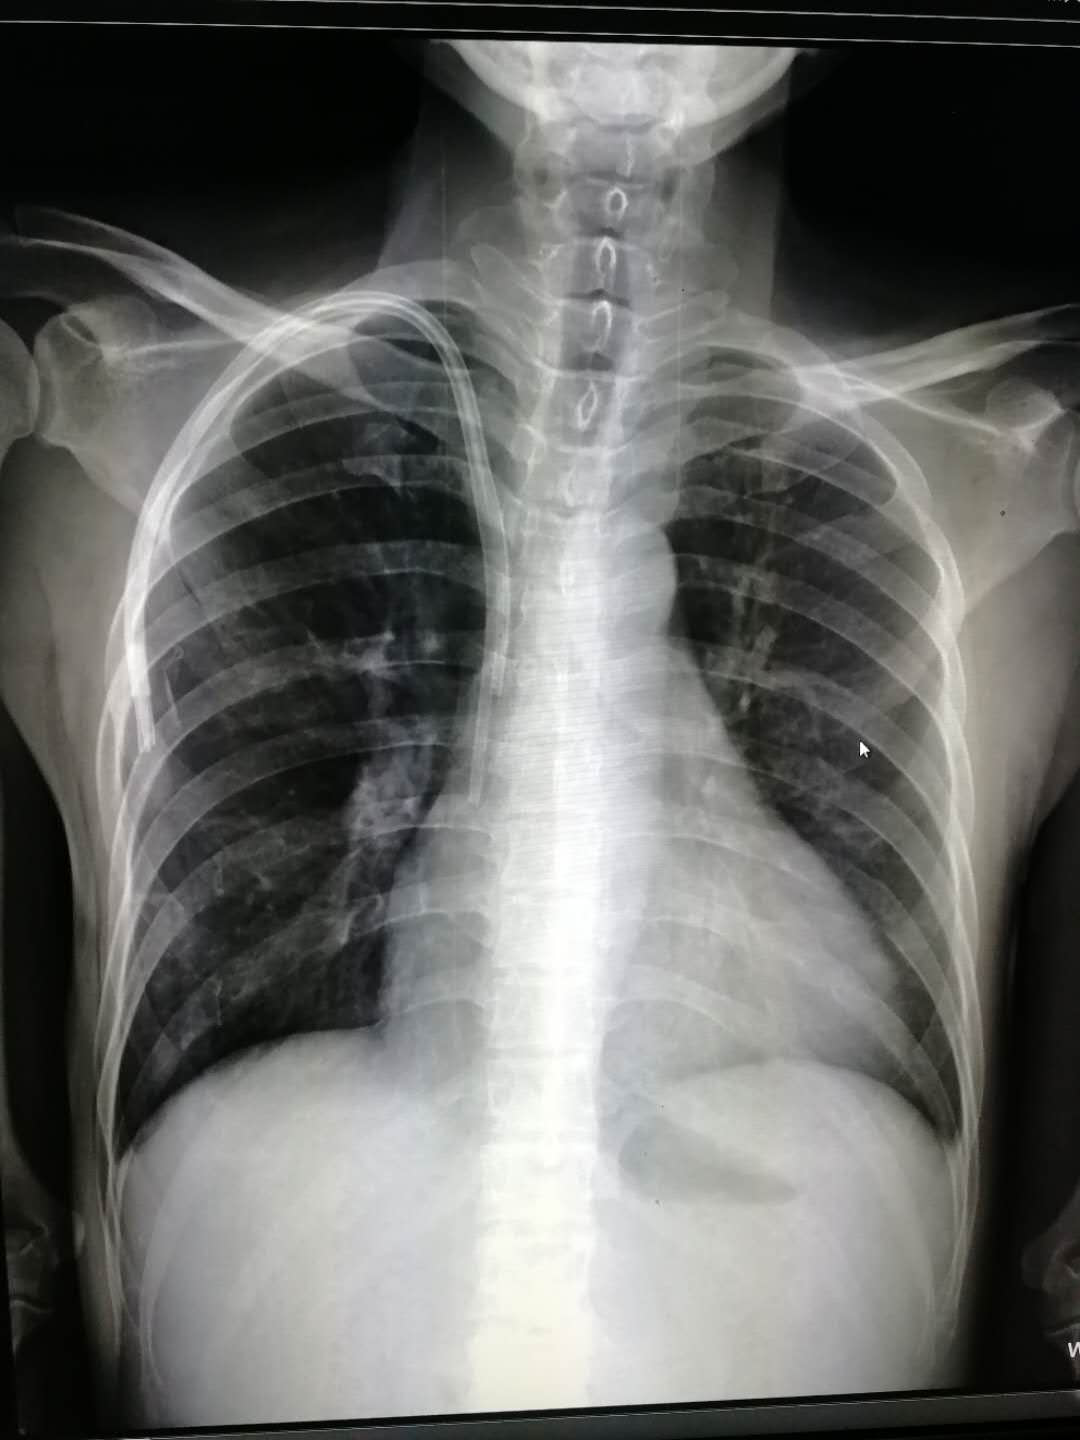

2019年1月24日,我院靜療小組在護理部的支持下開(kāi)展了“靜脈治療精細化、規范化管理”,特邀請放射科李月副主任,講解了“PICC導管靜脈解剖及影像知識”。

李月副主任從靜脈的結構、特點(diǎn)、分布及影像學(xué)角度進(jìn)行了詳細的講解,讓大家對靜脈解剖、影像有了更深一層的認識。靜療工作的開(kāi)展使我院護士根據科學(xué)方法為病人提供靜療服務(wù),從理論和操作實(shí)踐規范化培訓小組成員,從而提高護士對血管評估、保護能力及靜脈穿刺的操作水平,提高患者滿(mǎn)意度。